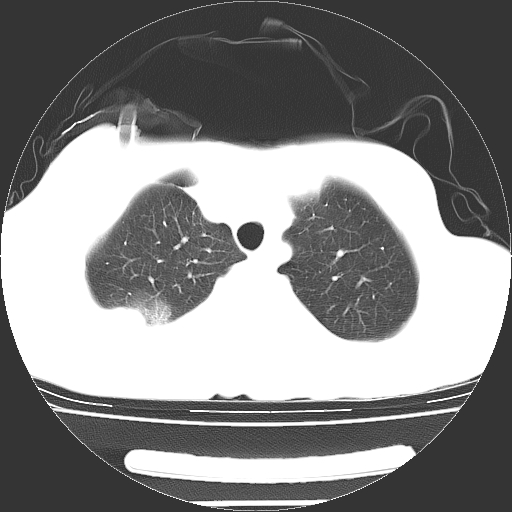

以下是引用dyqct在2008-4-29 8:43:00的发言:[br][br] 支持右侧胸腔包裹性积血。闭式引流管是不是插的太深了?

以下是引用zjzjr在2008-4-29 14:11:00的发言:[br]支持右侧胸腔包裹性积血。闭式引流管是不是插的太深了?胸腔引流,引流管快进入纵隔了.